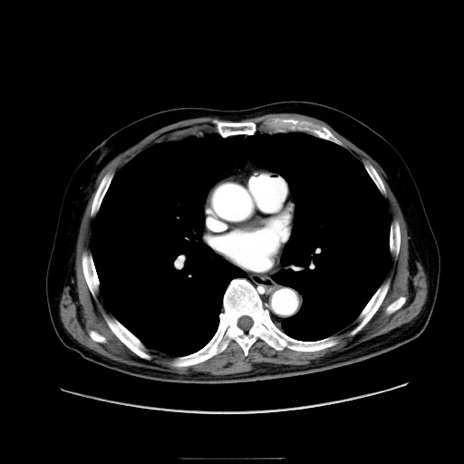

症例30(横断像)

【症例】80歳代男性

【主訴】臍周囲痛

【現病歴】約6時間前から臍下部痛が出現。次第に腹部膨隆・背部痛も生じてきたため来院。背部痛の場所は変化しない。

【身体所見】意識清明、BT 36.3℃、BP  131/87mmHg、P 87bpm、SpO2 100%(RA)、臍周囲自発痛・圧痛あり、反跳痛なし、自発痛部位に一致して板状硬あり、腹部膨隆、腸雑音減弱、CVA tenderness両側陰性。

【データ】WBC 19600、CRP 0.33